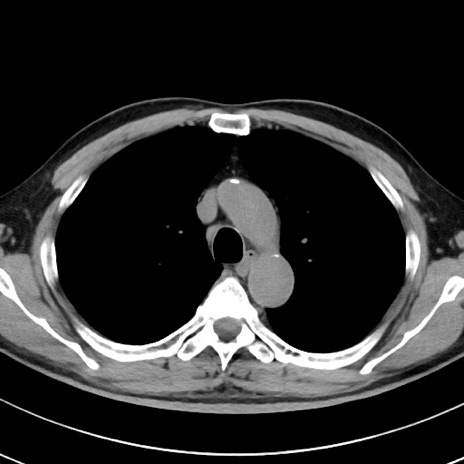

【腹部TIPS】症例29 参考症例 CT(横断像)

症例

70歳代男性